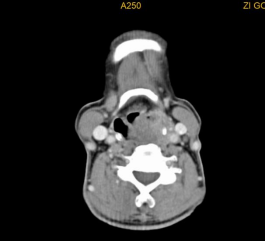

颈部恶性肿瘤在颈部肿块中占据很大比重,而80%的颈部恶性肿瘤为转移性恶性肿瘤,而这些转移性恶性肿瘤中80%的原发部位为头颈部,常见的有鼻咽癌颈淋巴结转移、下咽癌颈淋巴结转移、喉癌颈淋巴结转移,接下来我们来一一看看。

下咽部淋巴组织丰富,较易发生淋巴结转移,早期常转移至同侧颈动脉三角区颈深部淋巴结,多为分化程度较差的癌。而且由于下咽部位置隐蔽,常常原发灶不易发现,还有转移灶很大,原发灶很小的情况。

常见的还有口咽、口腔、鼻腔鼻窦癌颈淋巴结转移、甲状腺癌颈淋巴结转移等。颈部恶性肿瘤的诊断需要借助详细的病史、全面的体格检查及辅助检查(包括彩超、CT、电子鼻咽喉镜等),最重要的还是要去耳鼻咽喉头颈外科专科就诊。